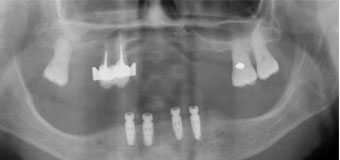

Il me manque de nombreuses dents, les autres sont perdues, je veux l’idéal.

Solution : on peut remplacer toutes vos racines manquantes ou perdues par autant de racines artificielles et vous redonner des dents fixes partout.

Toutes dents sont hélas perdues. Toutes les dents absentes sont remplacées par des couronnes sur implants.